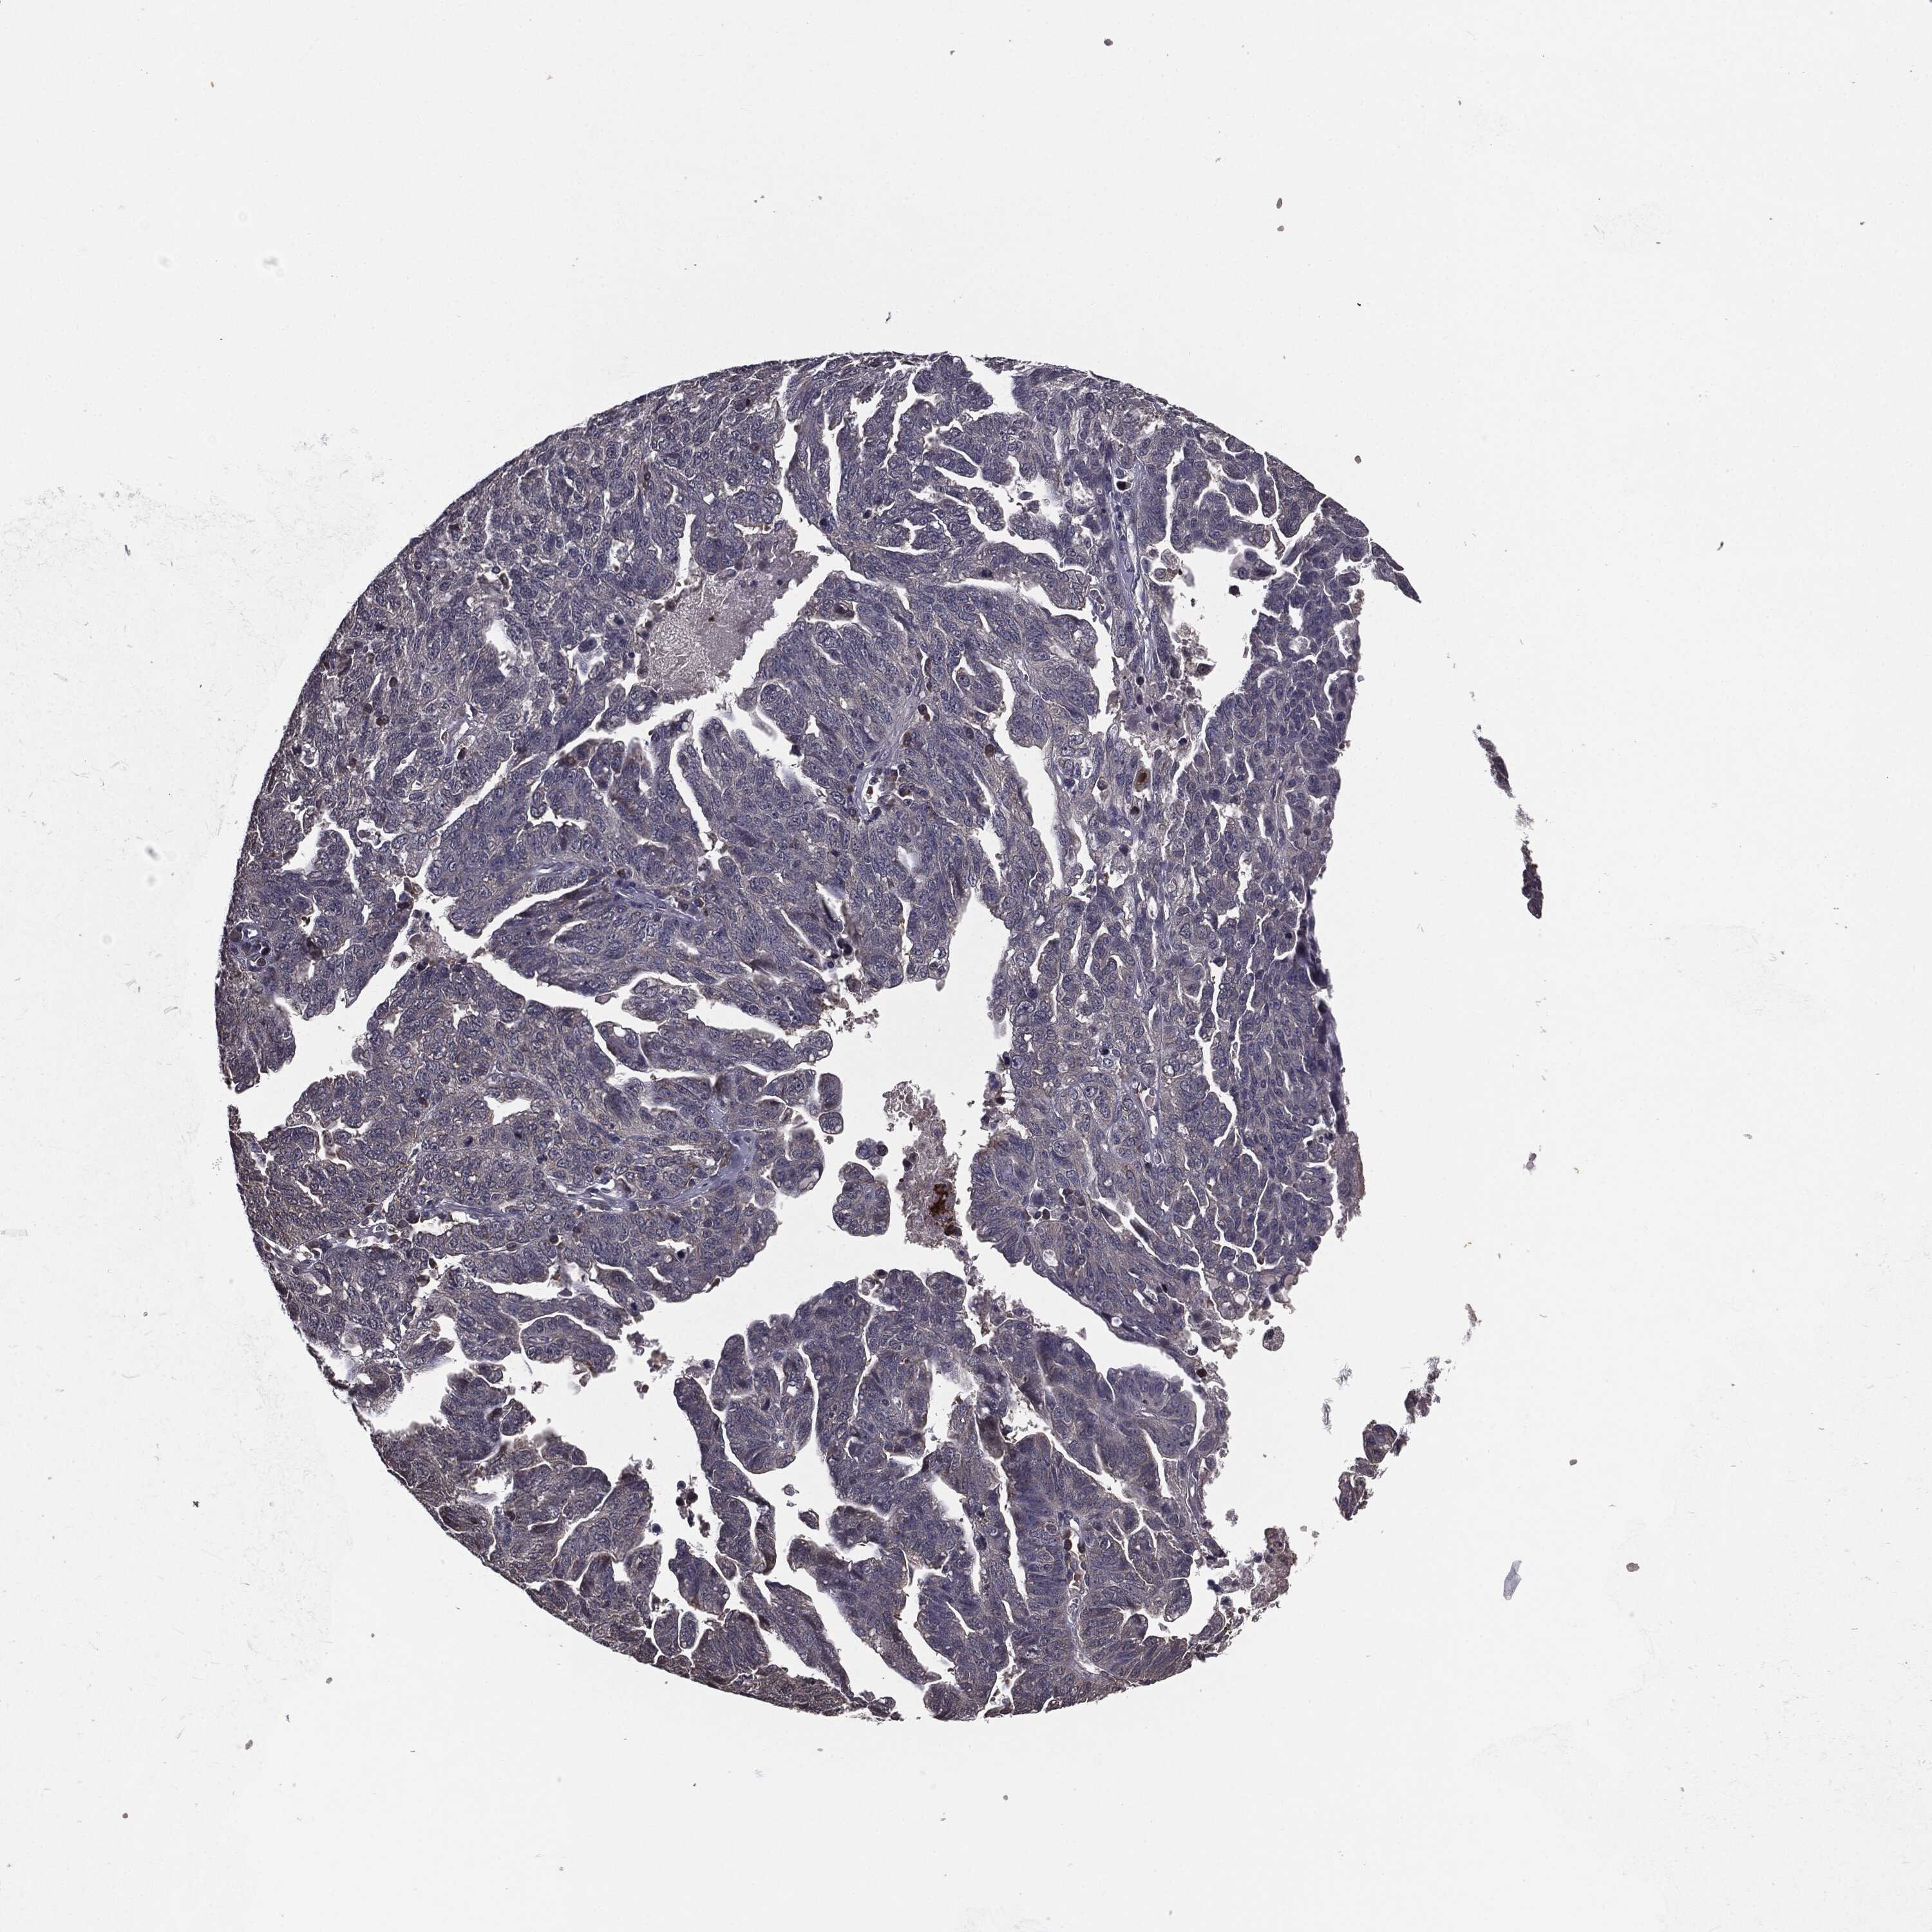

OVARIAN CANCER - Protein expressioni

A mouse-over function shows sample information and annotation data. Click on an image to view it in a full screen mode. Samples can be filtered based on level of antibody staining by selecting one or several of the following categories: high, medium, low and not detected. The assay and annotation is described here.

Note that samples used for immunohistochemistry by the Human Protein Atlas do not correspond to samples in the TCGA dataset.

Antibody stainingi

Antibody staining in the annotated cell types in the current human tissue is reported as not detected, low, medium, or high, based on conventional immunohistochemistry profiling in selected tissues. This score is based on the combination of the staining intensity and fraction of stained cells.

Each image is clickable and will lead to virtual microscopy that enables deeper exploration of all samples and also displays staining intensity scores, fraction scores and subcellular localization as well as patient and tissue information for each sample.

Antibody HPA077139

Cystadenocarcinoma, serous, NOS